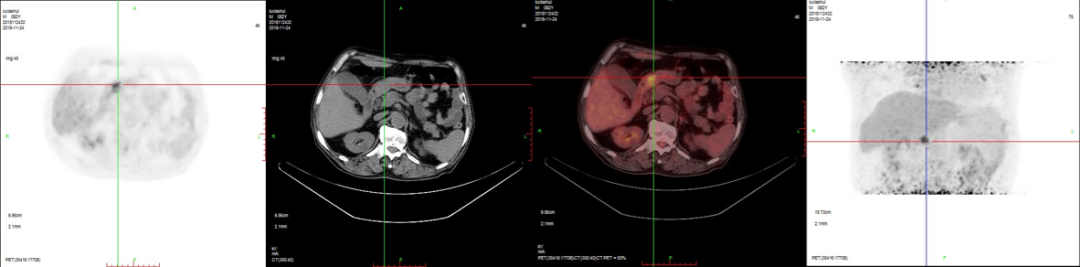

病例3:男性,72歲。結腸腺癌術后3年,右肺鱗癌術后1年隨訪。

PET/CT檢查:

1、全身多發骨轉移;

2、右側鎖骨區、縱膈及左側肺門多發淋巴結轉移;

3、腹膜后淋巴結轉移待排;

4、肝脾多發轉移灶可能。